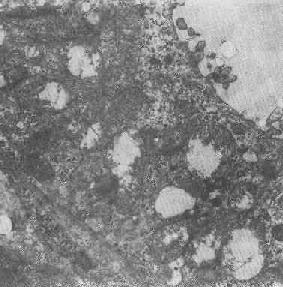

2.大小改变 细胞损伤时最常见的改变为线粒体肿大。根据线粒体的受累部位可分为基质型肿胀和嵴型肿胀二种类型,而以前者为常见。基质型肿胀时线粒体变大变圆,基质变浅、嵴变短变少甚至消失(图1-9)。在极度肿胀时,线粒体可转化为小空泡状结构(图1-10,图1-11)。此型肿胀为细胞水肿的部分改变。光学显微镜下所谓的浊肿细胞中所见的细颗粒即肿大的线粒体。嵴型肿较少见,此时的肿胀局限于嵴内隙,使扁平的嵴变成烧瓶状乃至空泡状,而基质则更显得致密。嵴型肿胀一般为可复性,但当膜的损伤加重时,可经过混合型而过渡为基质型。

图1-10肾小管上皮细胞线粒体部分空泡变